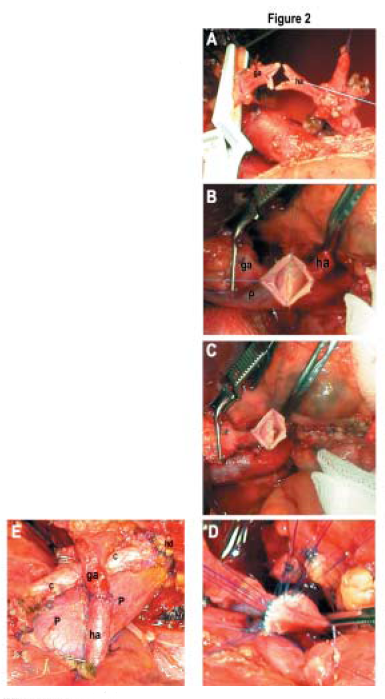

After the vessels have been washed with papaverine HCL solution, 2 untied stay sutures were placed at both corners of the arterial ends (Figure 1A). Native and graft hepatic arteries are spatulated approximately 1 to 2 mm from the anterior and posterior walls (Figure 1B), after which 2 retraction sutures are placed at the middle portion of the anterior wall of both recipient and graft arteries (Figure 1C, Figure 2A). A double-needle suture is then placed on the left corner of the posterior wall of both recipient and graft arteries. Then, 1 arm of that suture is continued to the right corner of the anastomosis (Figure 1D, Figure 2B). After the posterior wall of the anastomosis has been completed, both of the untied stay sutures on the left and right corners are tied with a running suture (Figure 1E, Figure 2C). The anterior wall of the anastomosis is sutured with interrupted sutures and completes the anastomosis (Figures 1F and 1G, Figures 2D and 2E).

Figure 2. A. Two untied stay sutures are placed at both corners of the arterial ends, anterior and posterior walls are spatulated about 1-2 mm, and 2 retraction sutures are placed at the middle portion of the both anterior walls of the arteries.

B. A double-needle suture is then placed at the left corner of the posterior wall of both recipient and graft arteries. Then, 1 arm of that suture is continued to the right corner of the anastomosis.

C. After finishing the posterior wall, both open loop stitch ends are pulled to the left and right corners to lessen the excess, and the posterior walls of both arteries are approximated tightly.

Next, both untied sutures on the left and right corners are tied.

D. The anterior wall of the anastomosis is sutured with interrupted sutures.

E. End of the anastomosis.